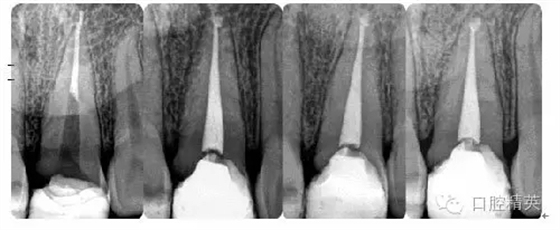

病例1:常規(guī)根管治療

病例4:根管再治療

病例5:遺漏根管再治療